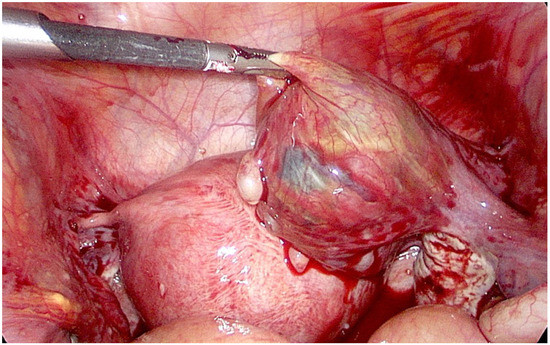

2. Case Presentation